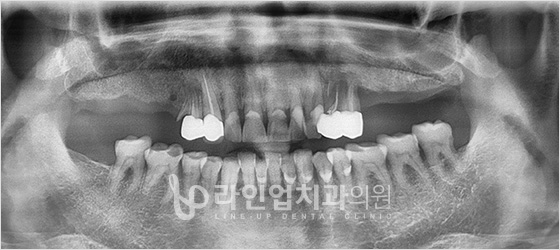

치료전

Before

치료후

After

윗 어금니 임플란트 (56세/남/ 2014.05.02~2014.10.06)